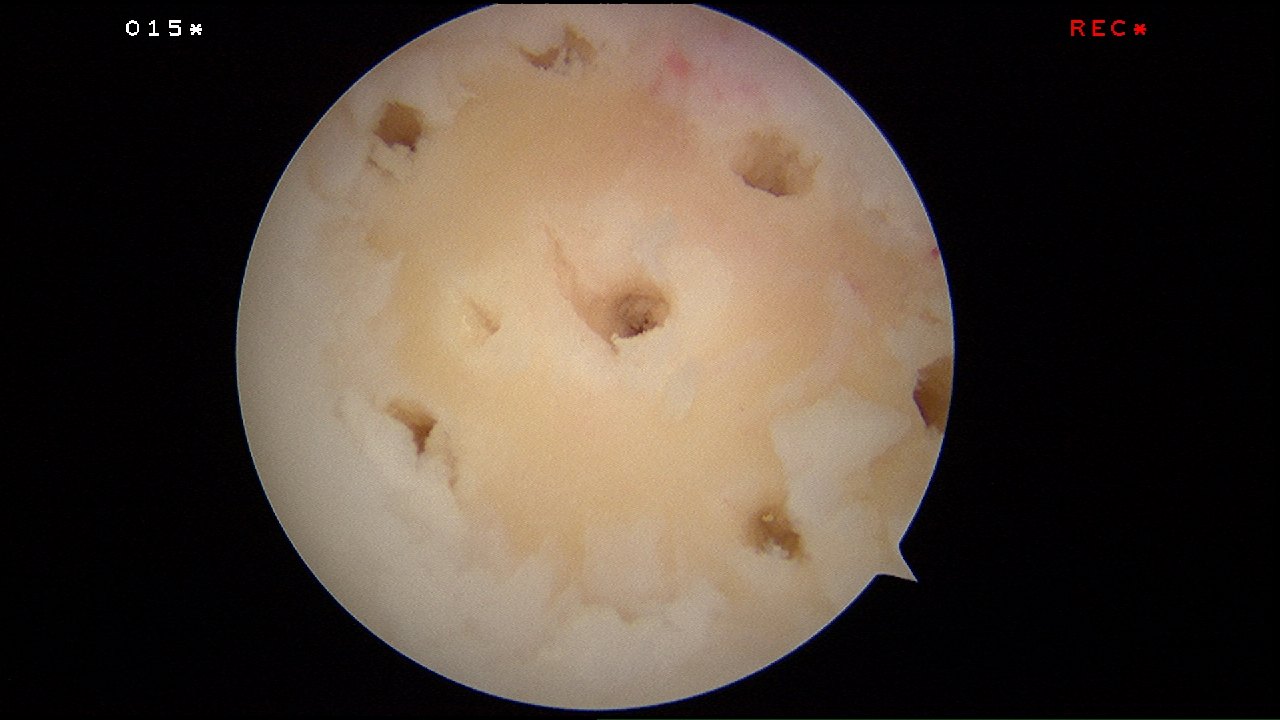

Microfracture surgery is an articular cartilage repair surgical technique that works by creating tiny fractures in the underlying bone.

The tiny microfracture holes cause bleeding from the underlying bone marrow and it forms a so-called super-clot.

The beauty of this surgery is that it is done through key-holes (using arthroscopy) and with easily available tools called chondral picks.